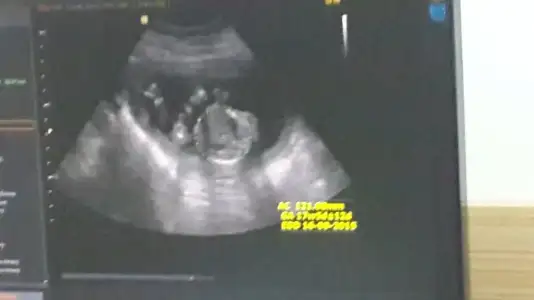

Kızlar bu bebişede bi yorum yaparmısınız arkadaşımın ama doktor büyük ihtimal kız dedi ama bide siz bakın bacak arası resmide var

Eklentiler

• 20150413_102628.webp

20150413_102628.webp

22,4 KB · Görüntüleme: 123

• 20150413_102513.webp

20150413_102513.webp

14,8 KB · Görüntüleme: 127